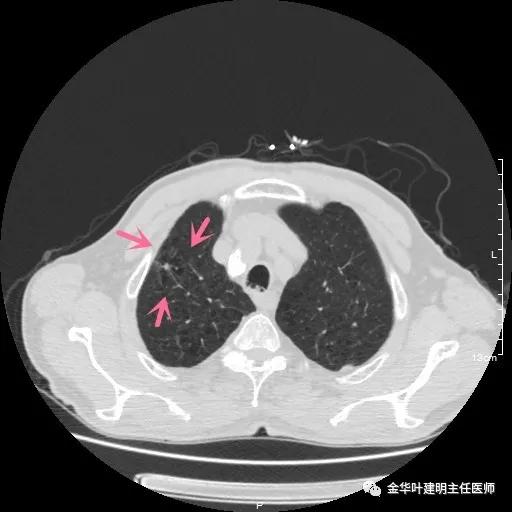

以上示右上病灶,我们称其病灶1。为囊腔型病灶,边缘为磨玻璃影,且轮廓清楚,局部有点状高密度,需考虑为囊腔型肺癌。单纯从单一病灶来看,这样的年纪可以随访或局部切除。